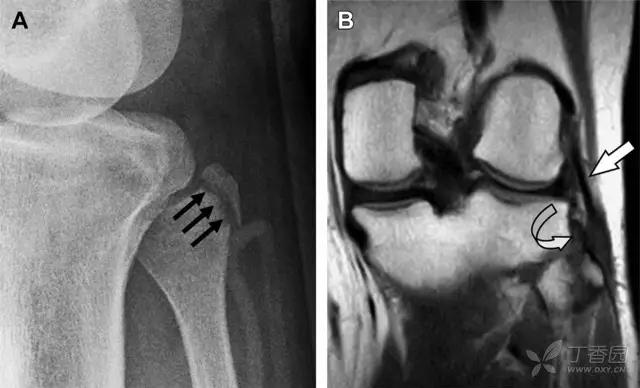

9 股骨外侧髁凹陷征

图 2 扭伤后的股骨外侧髁凹陷征

A 侧位片示股骨外侧髁凹陷。B MRI 矢状位 T2 加权像示股骨外侧髁及胫骨后外侧骨挫伤(空箭头)。胫骨近端随着后交叉韧带撕裂发生移位,露出外侧半月板的后角(弧形箭头)。